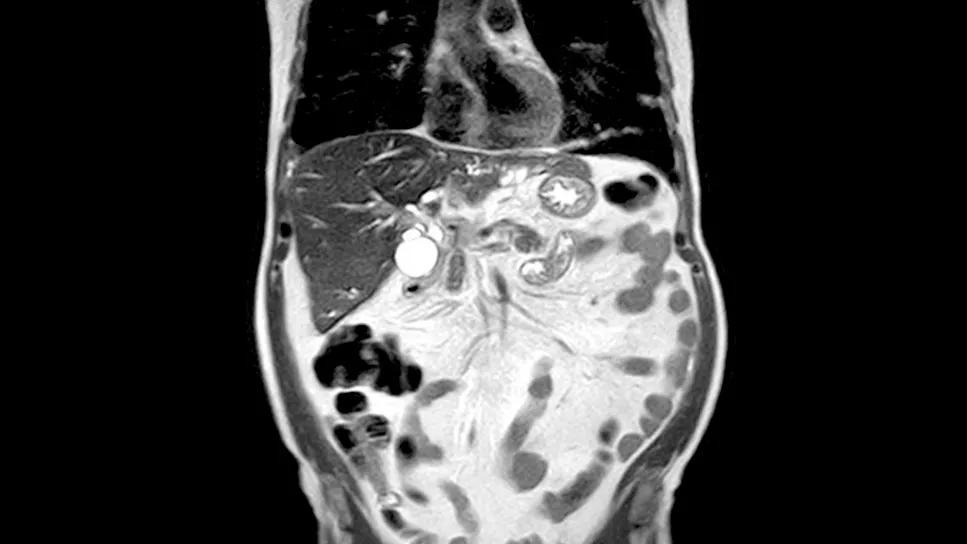

scan showing cholangiocarcinoma